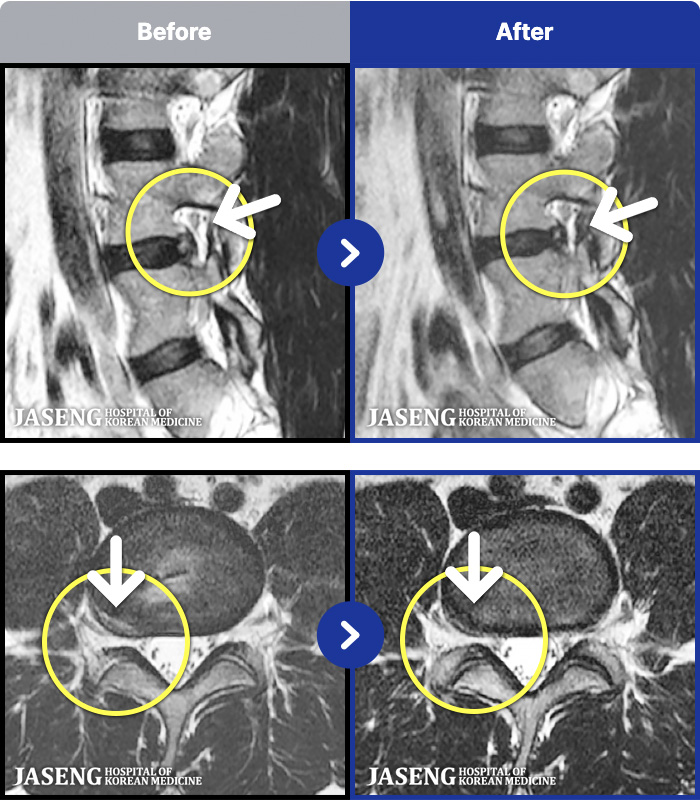

MRI ġ

1,237 MRI ũ ʸ Ȯϼ.

[Կñ:03.04.01~09.11.01]

[_㸮ũ] 㸮 , ٸ ̾ ϼ̽ϴ.

No.1236

ȸ 2,238

2025.09.22